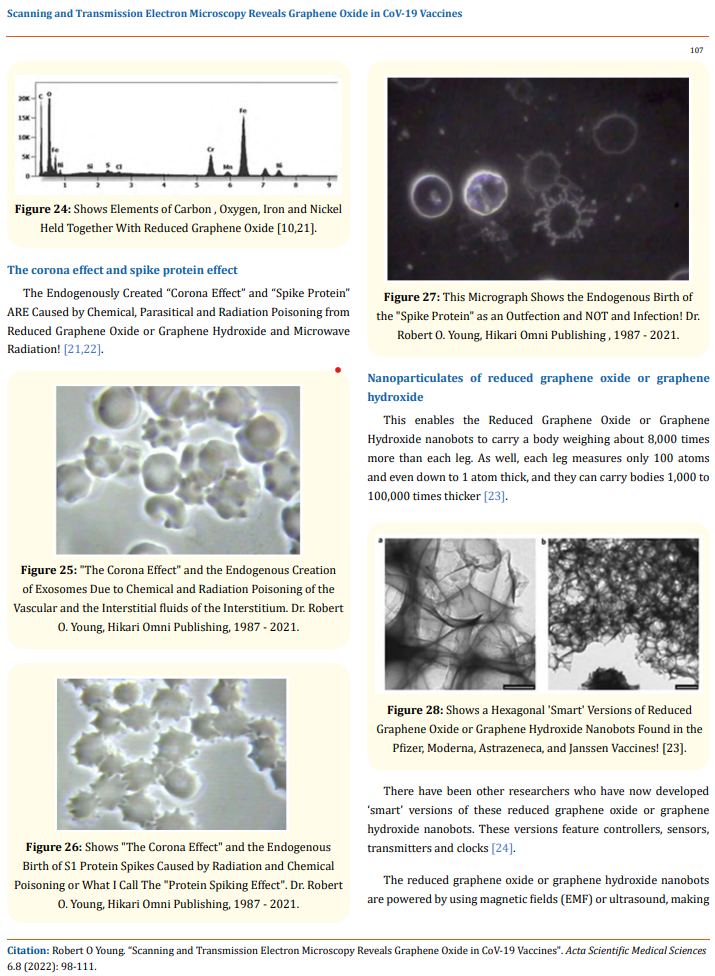

The Working Group for CoV VaXXXine Analysis states that some of the toxic elements found inside the AstraZeneca, Pfizer, and Moderna vaXXXine vials were not listed in the ingredient lists from the manufacturers. The following metallic elements were found in the vaXXXines:

From Published Research: Hikari Omni Media Publications, February 5th, 2021, “Scanning & Transmission Electron Microscopy Reveals Graphene & Parasites in CoV-19 Vaccines”, R.O. Young.

Abstract: Currently there are four major pharmaceutical companies who manufacture a SARS-CoV-2 now called SARS-CoV-19 vaccine. These manufactures and their vaccine are Pfizer–BioNTech mRNA Vaccine, the Moderna-Lonza mRNA-1273 Vaccine, the Serum Institute Oxford Astrazeneca Vaccine and the Janssen COVID -19 Vaccine, manufactured by Janssen Biotech Inc., a Janssen Pharmaceutical Company of Johnson & Johnson, a recombinant, replication-incompetent adenovirus type 26 expressing the SARS-CoV-2 spike protein.

The intended purpose of these vaccines are to provide immunity from the so-called infectious novel coronavirus or SARS-CoV – 2 virus now called the SARS-CoV – 19. These four pharmaceutical companies have not provided complete FDA disclosure on their vaccine box, insert fact sheet or label for many of the major and/or minor ingredients contained within these so-called vaccines. The purpose of this research article is to identify those specific major and minor ingredients contained in the Pfizer VaXXXine, the Moderna VaXXXine, the Astrazeneca VaXXXine and the Janssen VaXXXine using various scientific anatomical, physiological and functional testing for each SARS-COV-2-19 vaccine.

As a human right, governed under World Law by the Nuremberg Code of 1947, the vaccine specific ingredient information is critical, required and necessary to know so that any human from any country in the World can make an informed decision whether or not to consent to the SAR-CoV-2-10-19 inoculation. We have conducted the scientific testing on each vaccine and have identified several ingredients or adjuvants that have not been disclosed which are contained in these four SARS-CoV – 2 -19 vaccines.